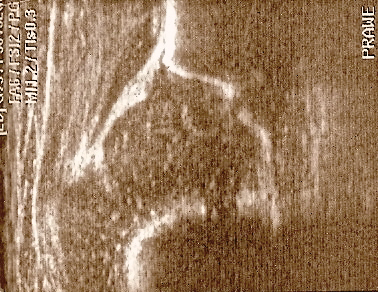

powyżej staw prawidłowy Typ I dach kostny dobry;brzeg kostny tępy ;dach chrzestny pokrywa

dolne zdjęcia

strzałki pokazują obrabek(czerwona):brzeg kostny (żółta);gałąż dolna(niebieska) ,

prawidłowy przebieg linii dachu kostnego(niebieska) stycznie do echa gałęzie dolnej i echa brzegu kostnego ;

linii dachu chrzęstnego (czerwona) stycznie do brzegu kostnego i przez środek geometryczny obrąbka i

linii podstawnej ( żółta

typ I czerwone kropki(od lewej) pokazują punkty do kreślenia 1 środek geometryczny obrąbka 2.brzeg kostny;3.gałąż dolną kości biodrowej

Typ IIc czerwone kropki od lewej) pokazują punkty do kreślenia 1 środek geometryczny obrąbka 2.brzeg kostny(dwa punkty);3.gałąż dolną kości biodrowej